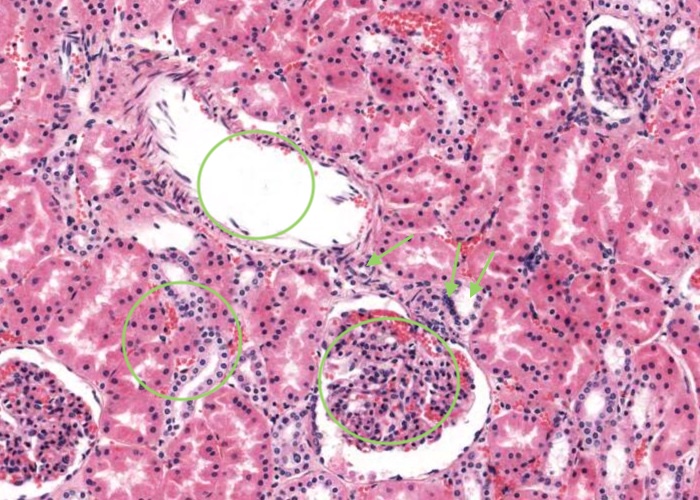

Interlobular arteries give off tiny afferent arterioles which run into the lobule to supply each renal corpuscle. An afferent arteriole enters a renal corpuscle, breaks up into a tuft of capillaries called a glomerulus, and then collects back into an efferent arteriole instead of a vein. This occurs at the "vascular pole". This is a nice image because it also shows part of a glomerulus with the urinary (tubular) pole visible (see more details in the next item). You may see an arteriole, but it will be impossible to tell whether it is afferent or efferent (although there is a slight hint that it is an afferent arteriole because it is adjacent to a distal convoluted tubule - ignore this though for now!). The efferent arteriole runs for only a short distance before breaking up into a second bed of peritubular capillaries, which nourish the proximal and distal tubules and absorb fluid. Even when these capillaries are collapsed you can easily see abundant red blood cells within their lumens between the convoluted tubules.

The distal straight tubule traverses the medulla into the cortex within a medullary ray and aligns itself adjacent to the vascular pole of the renal corpuscle with which it is a component. A clustering of nuclei of epithelial cells lining the distal straight tubule directly adjacent to the afferent arteriole in the vicinity of the vascular pole of the renal corpuscle form the "macula densa".

Each small interlobular artery (sometimes referred to as a "cortical radial artery") originates from the arcuate artery and then travels through the cortical labyrinth (containing the more eosinophilic proximal and the paler stained distal convoluted tubules) between adjacent medullary rays towards the kidney capsule. Some reach as far as the capsule and supply this outer covering of the kidney. An afferent arteriole supplying each glomerulus arises along the path of this interlobular artery or a number may arise from a common branch from the interlobular artery. I think there is an afferent arteriole supplying the glomerulus partly visible in this image because nearby is a macula densa in the wall of a distal straight tubule.